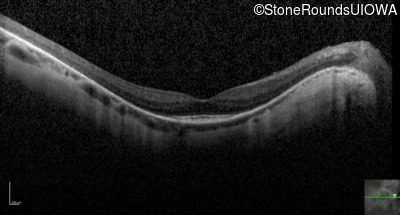

Optical Coherence Tomography - Right - 20/80 -1

Exemplar / OCT Stack

OCT Stack